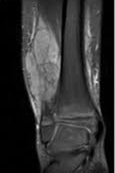

Pruebas de imágen

Las pruebas de diagnóstico por imágenes utilizan ondas sonoras, rayos X, campos magnéticos o sustancias radiactivas para crear imágenes del interior del cuerpo. Las pruebas de diagnóstico por imágenes pueden realizarse por diversos motivos, como:

Las imágenes más representativas o más comunes son:

5. Resonancia Magnética

2. Resonancia magnética